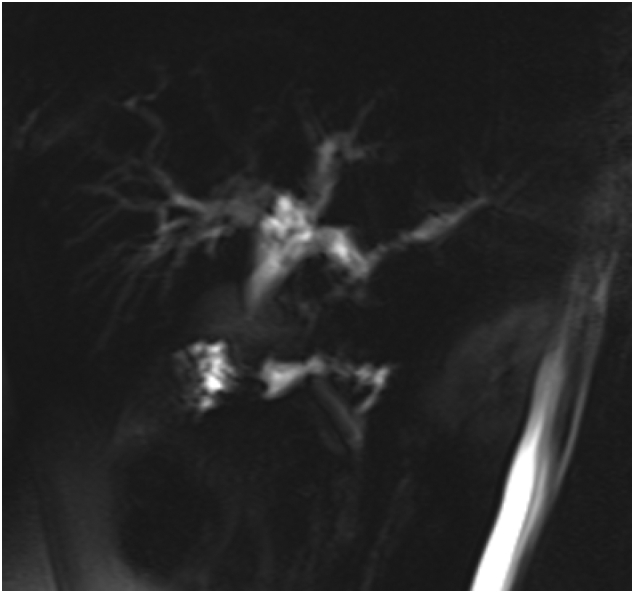

Magnetic resonance cholangiopancreatography (MRCP) [Fig. 1, Fig. 2] showed rounded porta hepatis soft tissue lesion measuring 2 ∗ 2.4 ∗ 2.8 cm, causing marked compression on common hepatic duct with proximal intrahepatic biliary tree dilatation and indenting the gallbladder fundus and Cystic duct.